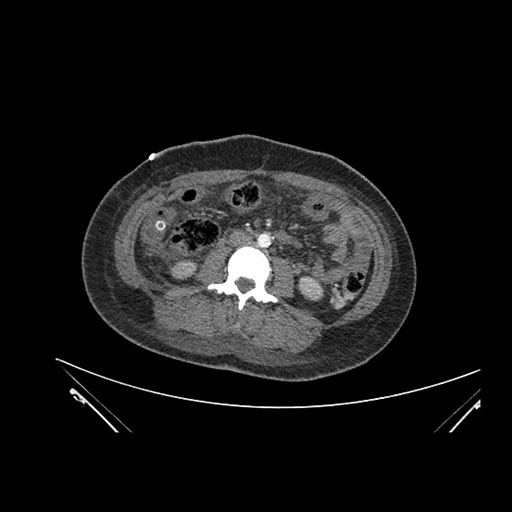

Axial Venous